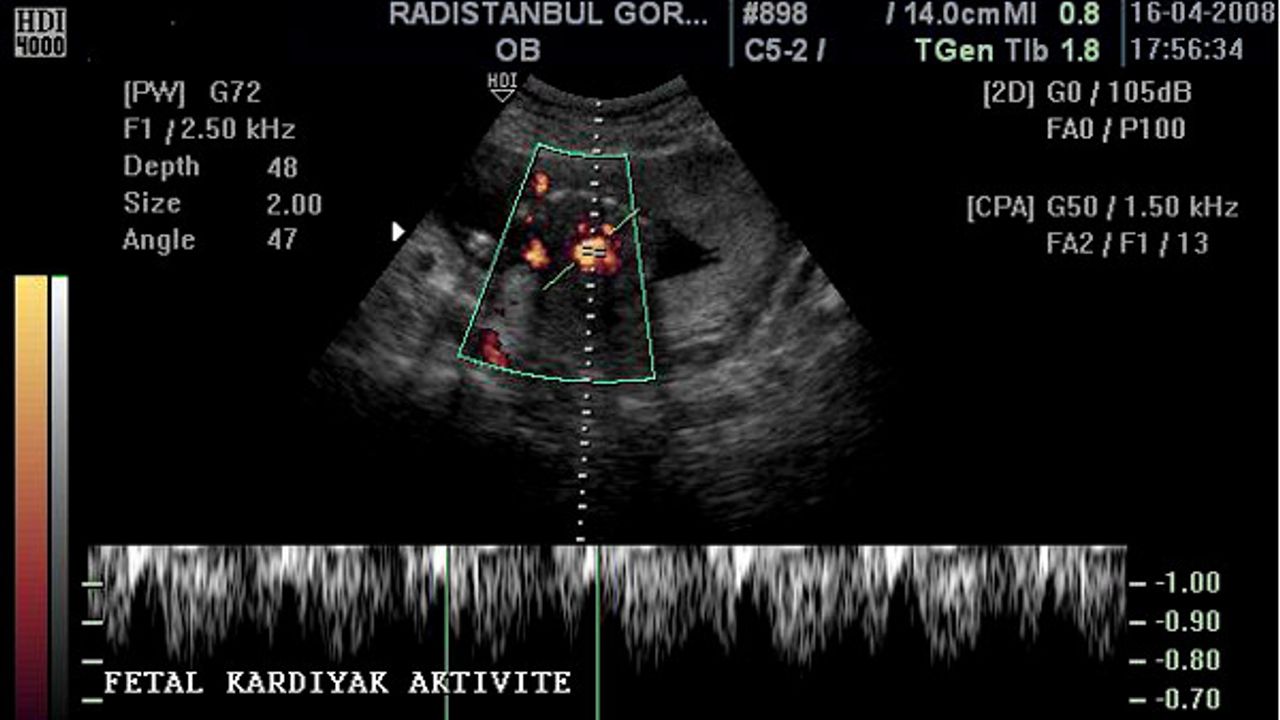

Doppler: Kan akışını ve kalp atışını inceleyen özel bir ultrason tekniği. Bebeğin veya organların dolaşımını değerlendirmede kullanılır.